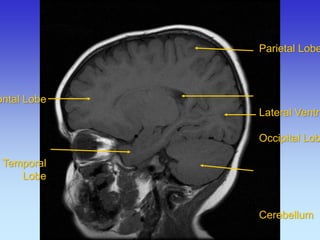

Sagitalni presjek

Frontal Lobe Lateral Sulcus

Parietal Lobe

Temporal Lobe

Frontal Lobe

Temporal

Lobe

Occipital

Cerebellum